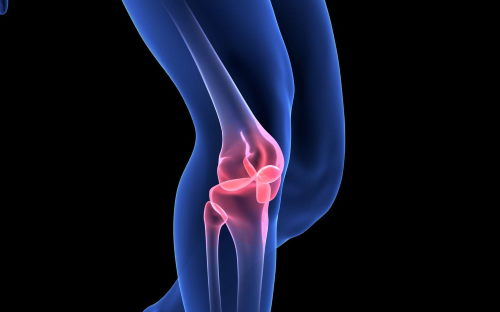

Avec l’âge, les os du squelette humain perdent peu à peu de leur densité et de leur matière. C’est un phénomène naturel lié au vieillissement et à la modification de notre patrimoine hormonal, vers la cinquantaine. Heureusement, des solutions naturelles existent pour pallier ces carences.

Du fait de la ménopause, les femmes sont plus touchées que les hommes par cette fragilisation osseuse sans pour autant parler d’ostéoporose qui en est la forme la plus sévère. Mais les hommes ne sont pas à l’abri de cette perte de leur capital osseux. Chacun tirera des avantages certains en termes de santé générale et de robustesse de son ossature en s’intéressant de près à ce qui peut renforcer les os.

La matière première des os est le calcium que l’on trouve en très grande quantité sur la Terre. À la différence des blocs calcaires, le calcium du squelette n’est pas agencé en bloc mais en minuscules « colonnes » imbriquées dans tous les sens. Cette structure, plus proche de l’assemblage des fines poutrelles de la Tour Eiffel que de l’entassement de pierres de la Pyramide de Gizeh, confère à nos os une grande résistance et une bonne légèreté.

Quand nous commençons à moins bien fixer le calcium, nos os se fragilisent. La première des solutions est donc de ralentir cette perte et d’améliorer nos apports quotidiens.